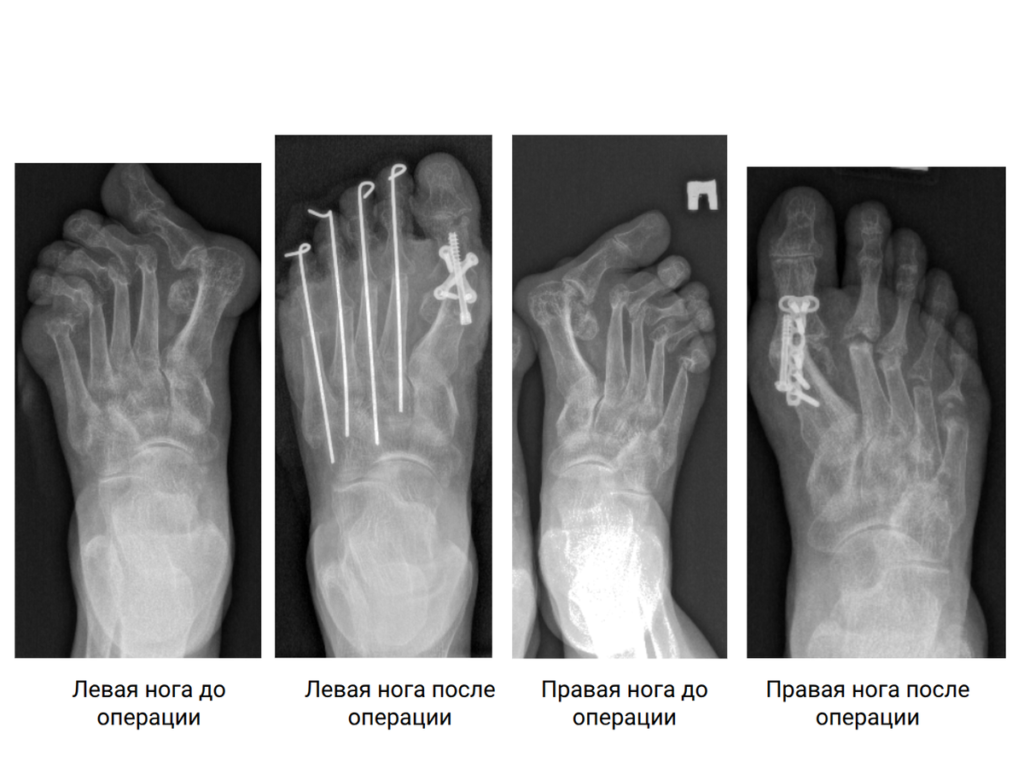

На обеих стопах — деформация пяти пальцев с разрушением головок плюсневых костей. Требовалось хирургическое лечение. Реконструктивное вмешательство носит название «операция Клейтона-Хоффмана». Специалисты выполняют корригирующий артродез первого плюснефалангового сустава, резекцию головок 2-5 плюсневых костей, вправляют вывихи малых пальцев и фиксируют спицами.

«К сожалению, не было речи о том, чтобы сохранить полностью кость, первый плюснефаланговый сустав — они были разрушены.

Нашей задачей было исправить деформацию и стабилизировать этот сустав — сделать первый луч стопы опорным, чтобы он был зафиксирован в функционально выгодном положении, и пациентка могла осуществлять перекат стопы (движение, когда вес переносится с пятки на носок при ходьбе). При этом добиться надёжной фиксации, без какой-либо дальнейшей тенденции к смещению.

Малые пальцы (2-5) были в состоянии вывиха, и пациентка испытывала постоянный дискомфорт, давление. Мы убрали разрушенные давящие головки плюсневых костей, тем самым добиться снижения напряжения на тканях. Пальцы встают в правильное анатомичное положение, уходит подошвенное давление», — объясняет к.м.н., хирург-ортопед Новосибирского НИИТО им. Я.Л. Цивьяна Минздрава России Матвей Лучшев.

Стопы становятся функциональными, кроме того, корректируется эстетический дефект. Ситуация на обеих ногах у пациентки была идентичной, но между операциями нужна хирургическая пауза — это необходимо, чтобы оперированная первой нога стала полностью опорной и могла воспринимать нагрузку.